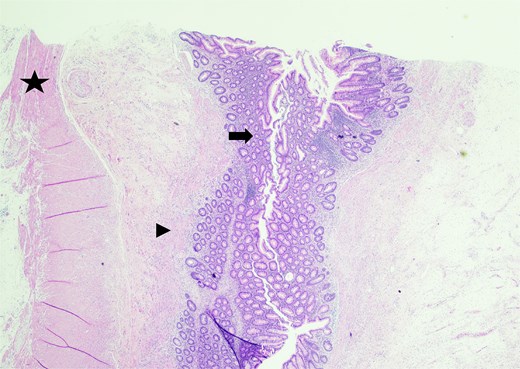

In the operating room, multiple adhesions from the patient’s prior colostomy site and colon resection were noted. The appendix was found to be dilated, acutely inflamed, and hyperemic, consistent with the suspected diagnosis of acute appendicitis. Adhesions from the appendix to the abdominal sidewall were dissected bluntly, pulling the appendix to a more medial position. The harmonic surgical device was used to divide the appendix mesentery and the gastrointestinal anastomosis (GIA) stapler with a blue load was used to divide the appendix from the base of the cecum. Final pathology showed an intact vermiform appendix measuring 6.5 × 1.5 cm with 3.2 × 2.5 × 1.6 cm portion of the attached mesoappendix. On gross examination, tan-pink hemorrhagic serosa with minimal adhesions and no exudate was noted. Sectioning of the specimen revealed a 0.5-cm in diameter lumen filled with a moderate amount of hemorrhagic purulent fecal material and at the distal tip, an intact diverticulum with wall measurement up to 0.2 cm in average thickness (Figs 1 and 2).

Sectioning of the intact vermiform appendix, bottom portion, with the appendiceal diverticula showing the muscularis propria (star) and acute inflammatory cells, neutrophils (arrowhead), within.